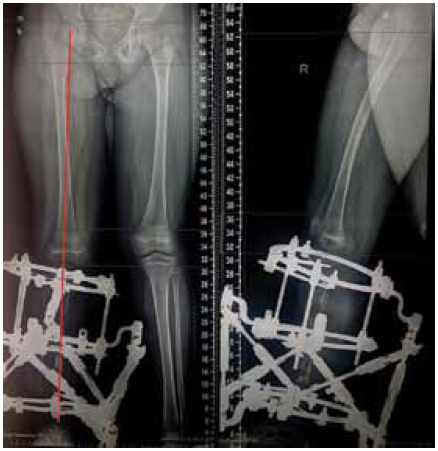

The second stage of treatment was the recommended correction of the resulting multiplane deformities of the affected lower extremity (mMPTA was 94°, mLDTA was 71°, aPPTA was 90°, and aADTA was 59°, shortening the affected lower limb by 8.0 cm). For lengthening and deformity correction of the right lower limb, the patient underwent preoperative planning for deformity correction with the exception of osteotomies in the area of consolidated pseudoarthrosis at the age of 9 years. According to the plan, a two-level osteotomy of the shin bones was performed, as along with lengthening by 5 cm by the Ilizarov method. The deformity was corrected using a repositional unit with Ortho-SUV computer navigation properties. The period of deformity correction was 58 days, and the external fixation period was 247 days. At the end of the fixation period, a recurrence of deformities of the tibial bones was detected with the formation of a deformity apex at the level of the proximal and distal tibial growth zones (mMPTA was 94°, mLDTA was 82°, aPPTA was 86°, and aADTA was 80°) (Fig. 1–4). We applied hemiepiphysiodesis to correct the recurrence of valgus deformity of the tibia. The period of deformity correction was 269 days. The reference angles values of the tibia were within the accepted ranges.

Fig. 5. Photographs of the patient after the disassembly of the external fixation device and the application of hemiepiphysiodesis to correct the recurrence of deformities: а — frontal view; b — lateral view

Fig. 6. Radiographs of the patient after the disassembly of the external fixation device and the application of hemiepiphysiodesis to correct the recurrence of deformities: а — anterior-posterior view; b — lateral view